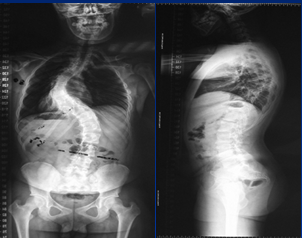

术前照片